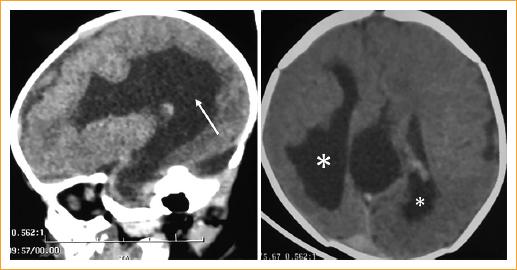

Paciente de sexo femenino de 1 mes de edad que se presenta al departamento de genética con antecedentes de epilepsia, agenesia total del cuerpo calloso y disgenesia vertebral con escoliosis, los cuales fueron identificados durante la evaluación neurológica previa (Fig. 1). Fue producto de tercera gesta de padres no consanguíneos y nació por cesárea con embarazo de término sin complicaciones. No requirió maniobras de reanimación cardiopulmonar avanzada, el peso al nacer fue de 2,900 g y la talla fue de 49 cm; se desconocen las puntuaciones en las escalas de Apgar y Silverman-Anderson.

Figura 1 Imágenes de tomografía que muestran agenesia total de cuerpo calloso (flecha) y heterotopia cortical (asteriscos).